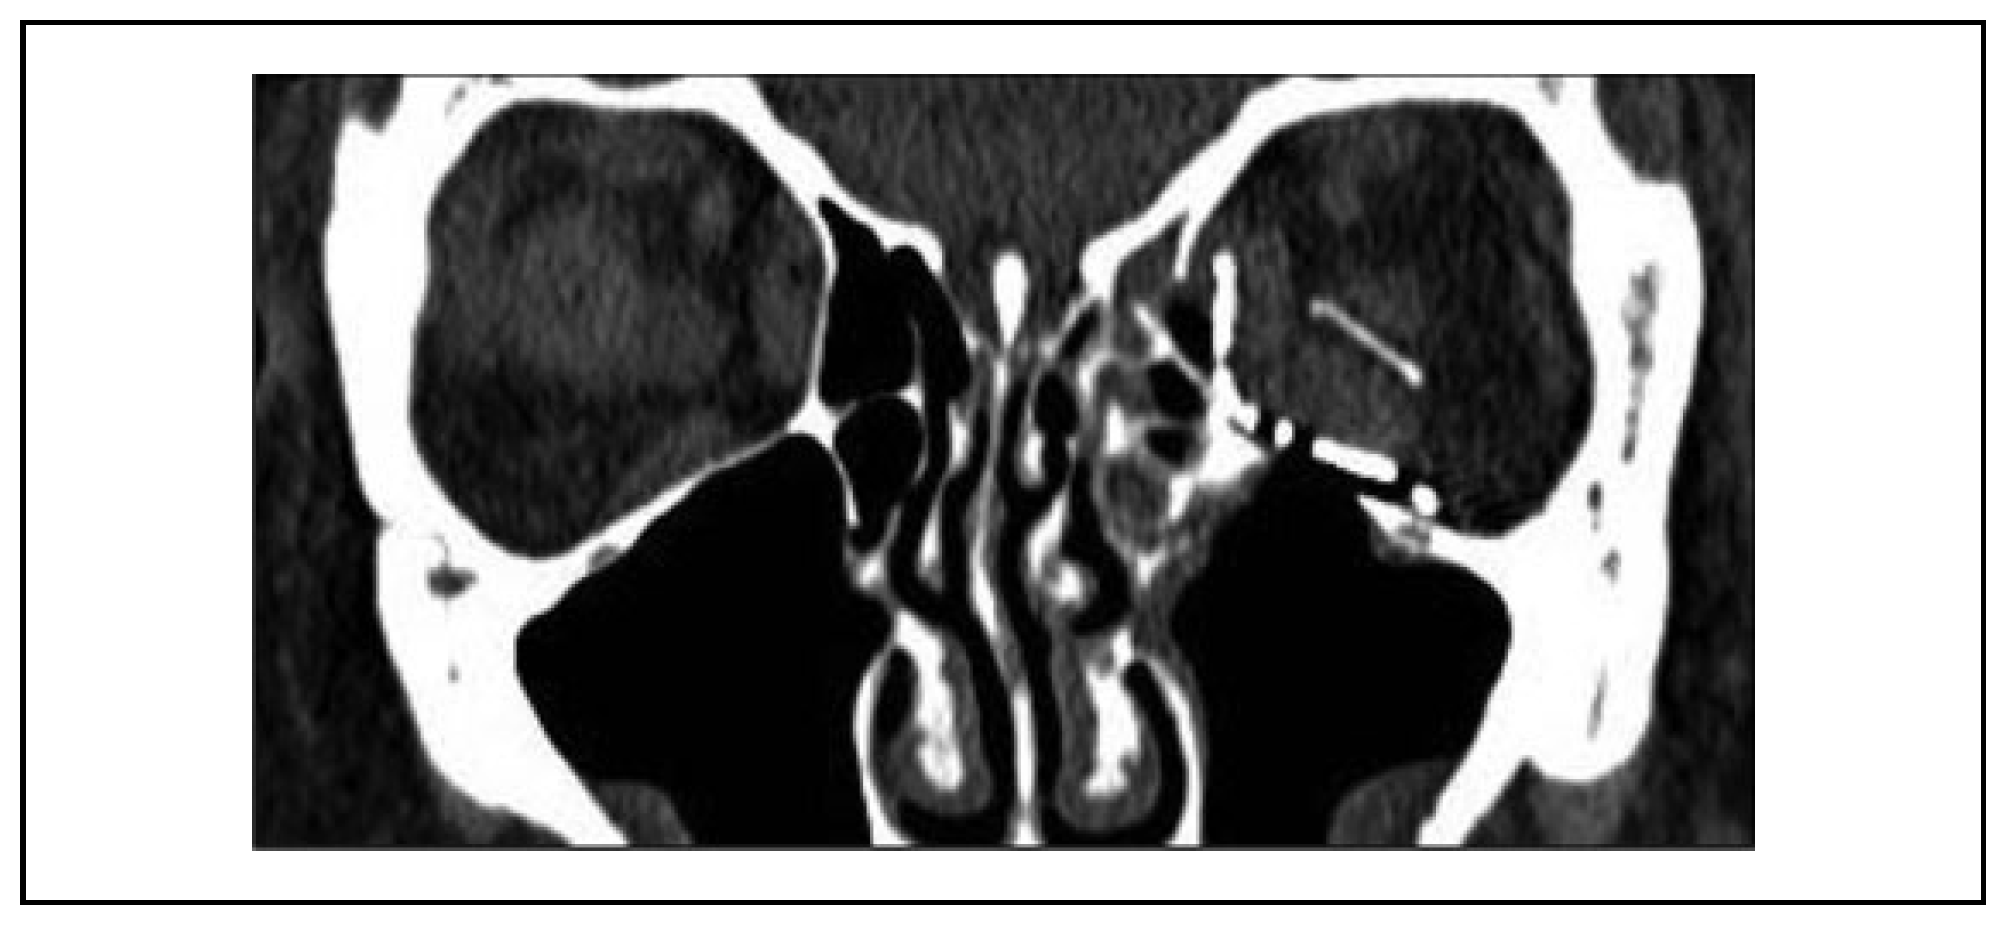

Case Report